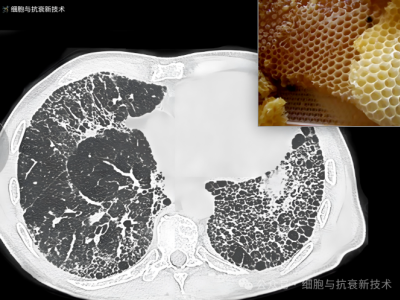

外泌體霧化可治療肺部結節及肺纖維化

2019年新冠疫情后,大家對肺部損傷比較關注,加之生活工作壓力以及檢測技術的進步,使結節成為體檢報告上出現的高頻詞匯,其中包括肺部結節,結節的出現給部分人群增添了焦慮。外泌體作為先進治療藥品,是當前生